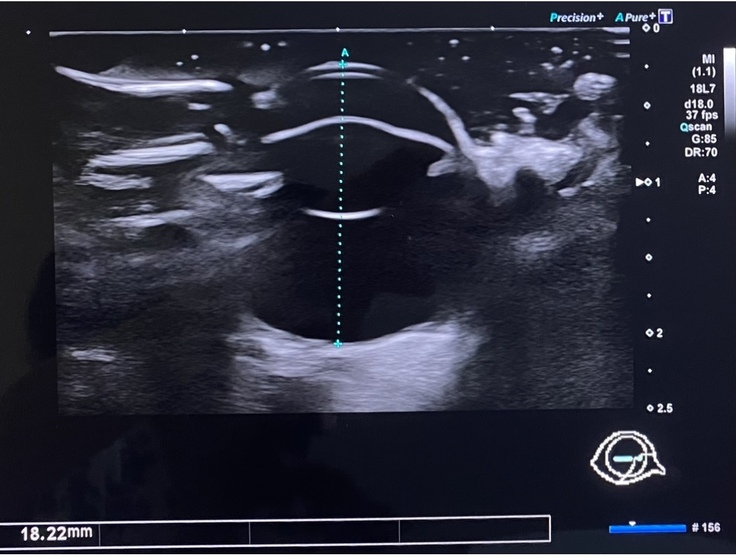

正常な右目は大きさが18mmあるのに対し、

損傷した左目は11mまで小さくなってしまいました。この後、5mmほどまで萎んでいく可能性があるそうです。

上から目を見た状態です。こちらが正常な右目。直径18.22mmあり、中の組織も綺麗です。

こちらが損傷した左目。直径11.2mmまでしぼみ、目の内部の組織も壊れてしまっています。